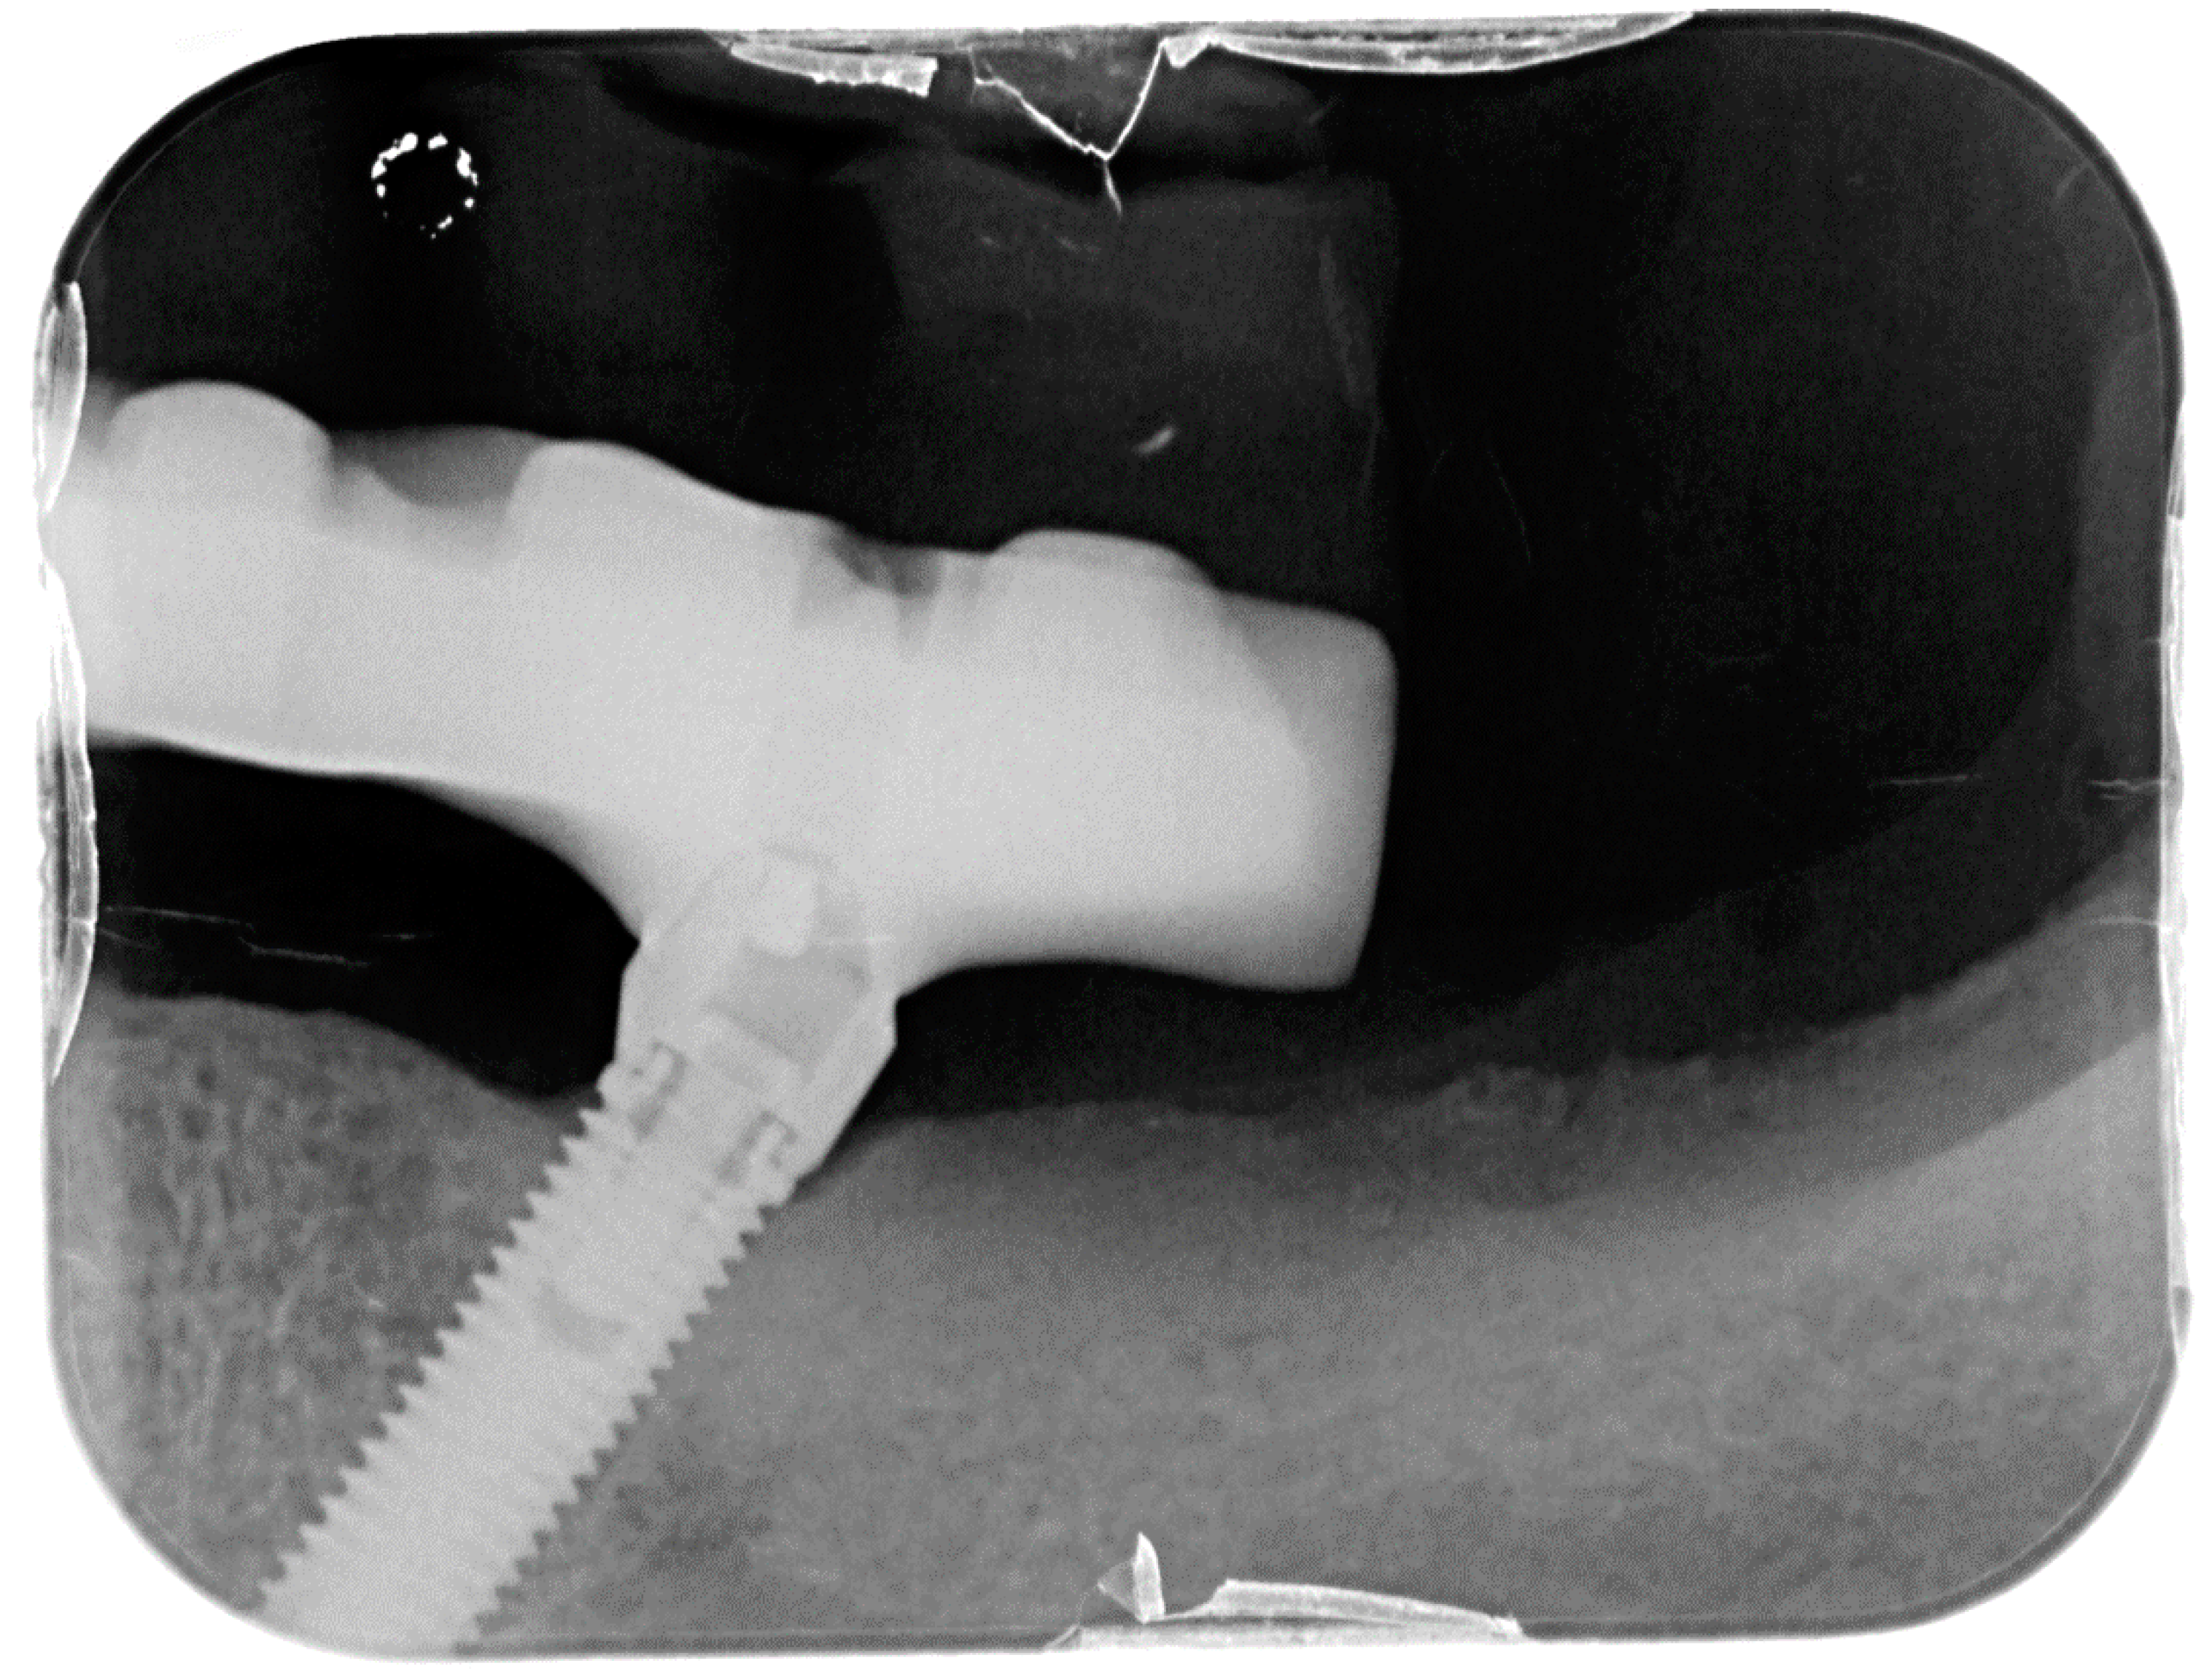

Figure 2.

X-ray of dental implant area before treatment.